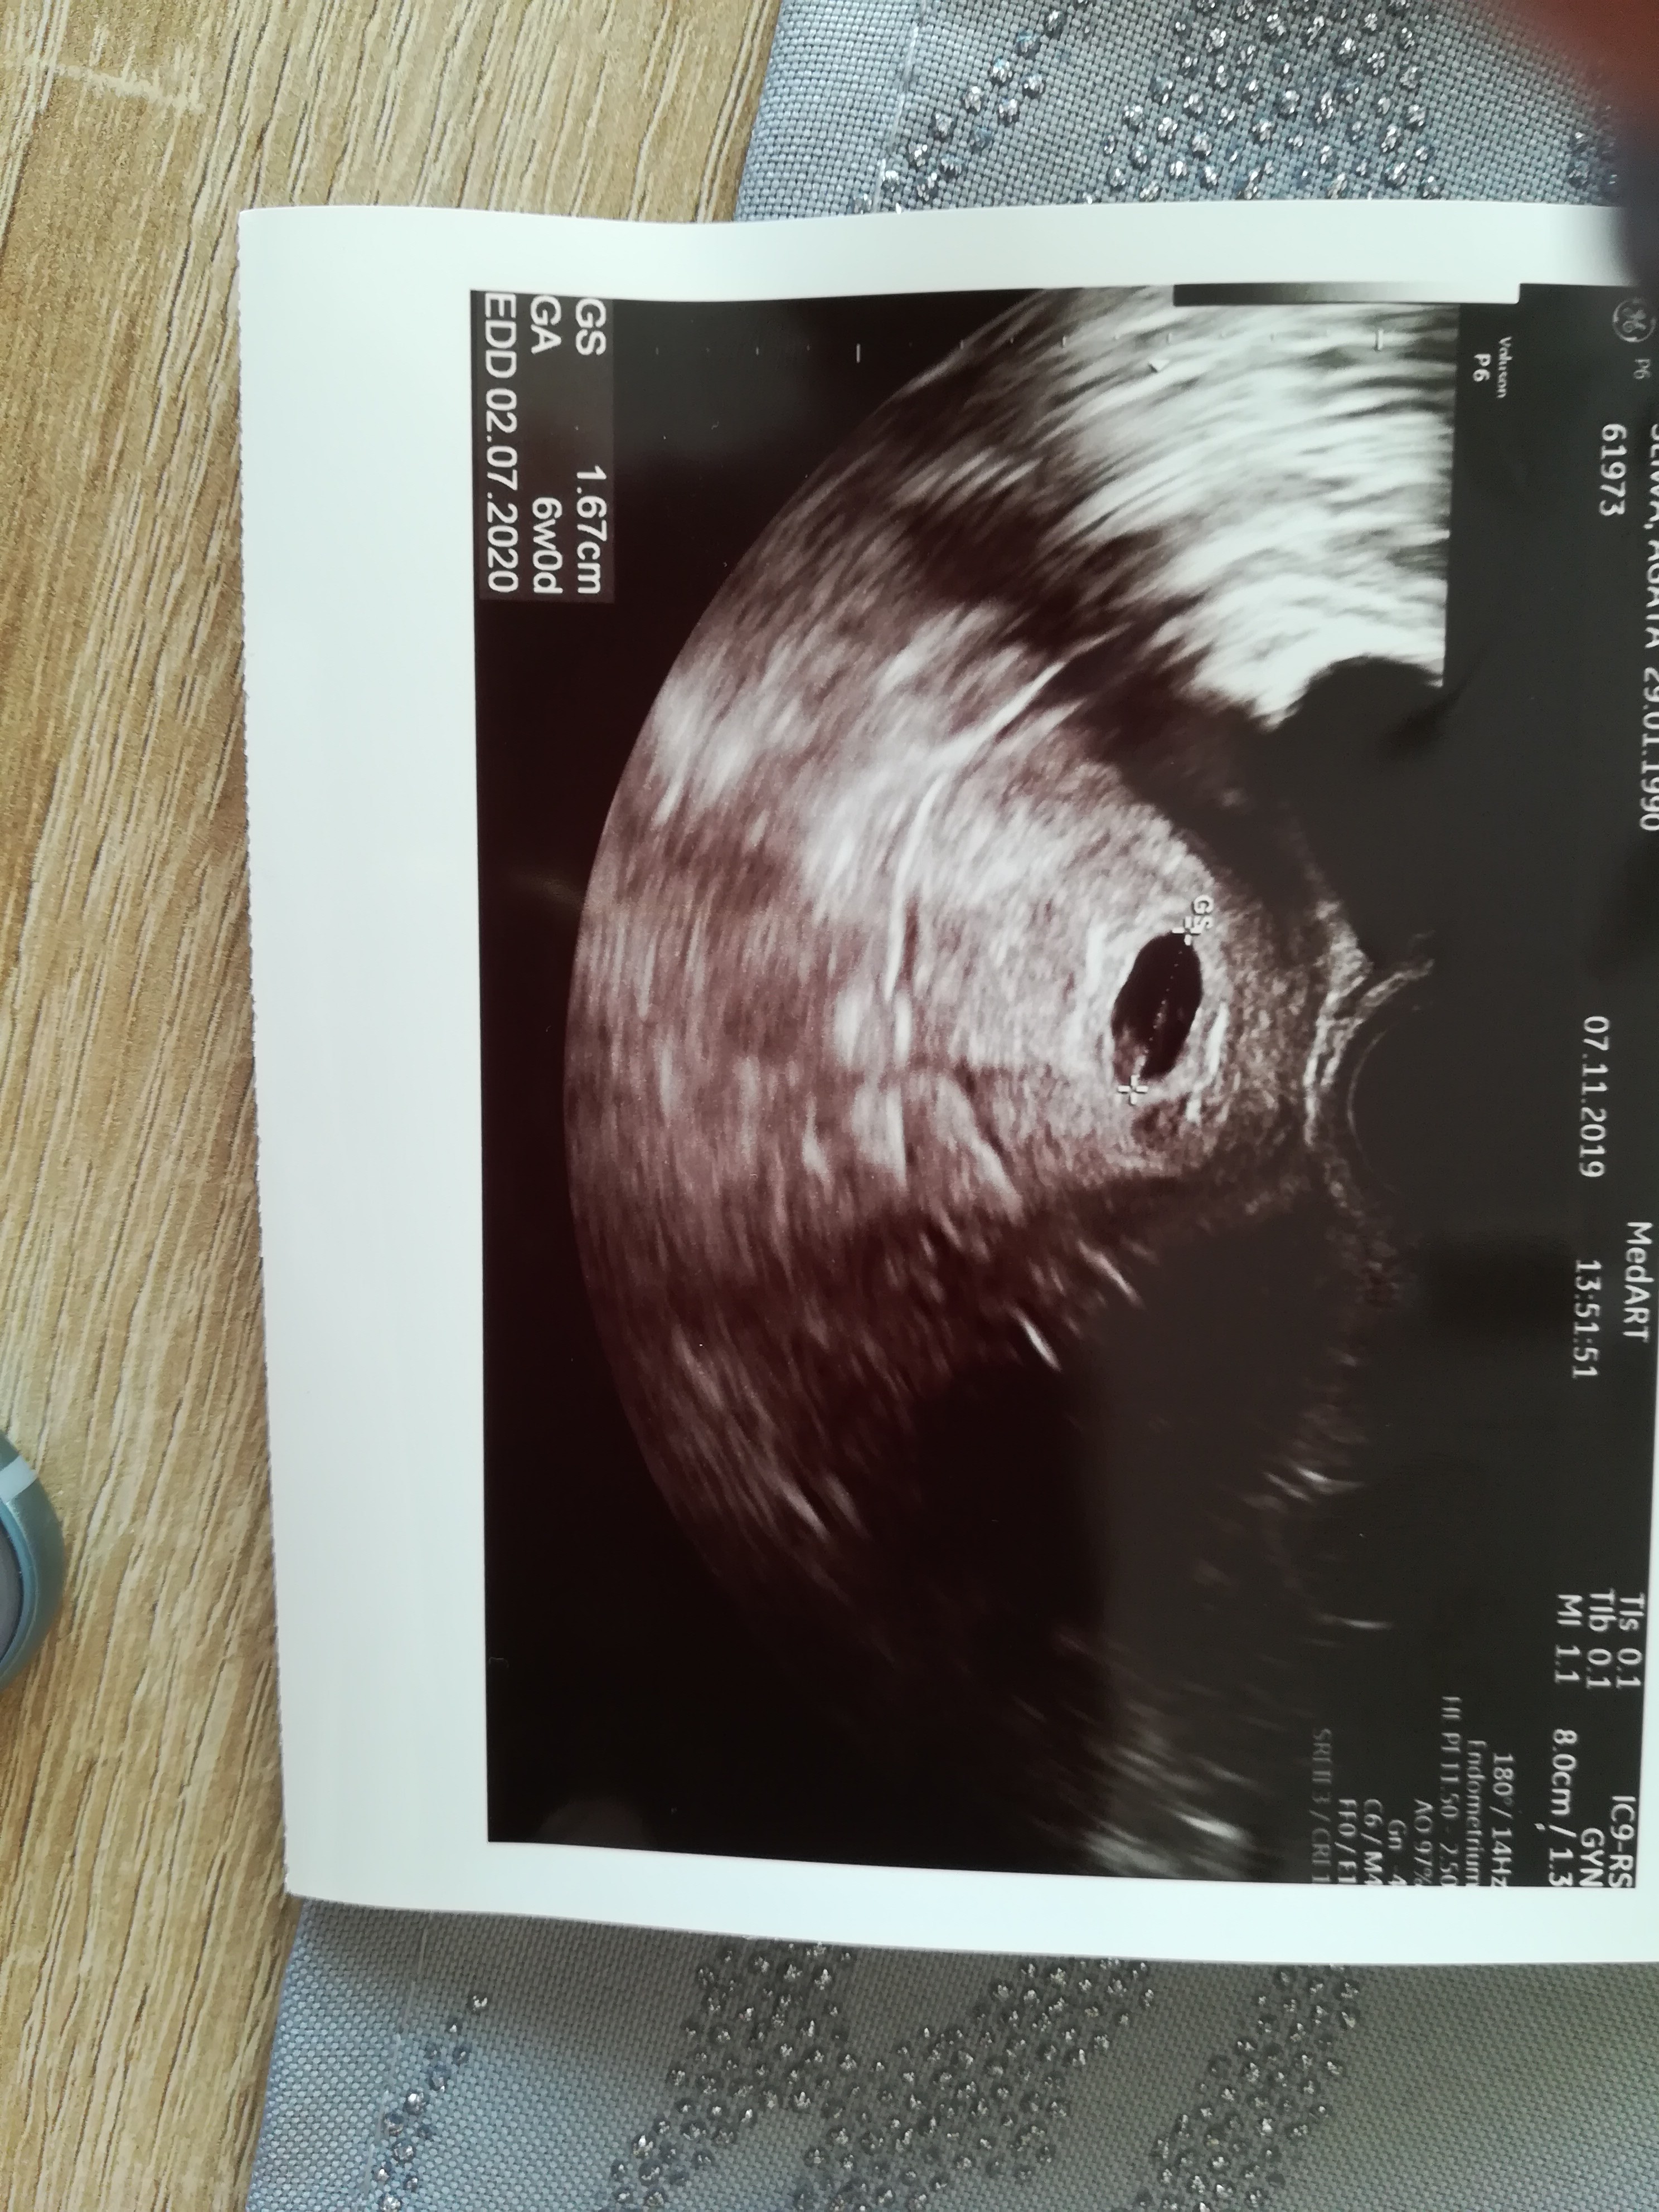

To dzisiaj miałaś USG? Nie wiem czemu ubzduralam sobie że masz jakoś w przyszłym tygodniuDziewczyny dzisiaj zobaczyłam mój pęcherzyk ciążowy i oszalałam ze szczęścia ❤ proszę o wpisanie 21.11 wizyty serduszkowej do kalendarza ☺Zobacz załącznik 1042395

Super kochana A o tym plamienia coś mówił?widzisz ja też non stop plamie krwawie A wszystko jest okU nas wszystko superkropek rozwija się książkowo i nawet widziałam echo serca bo na liczenie ponoć jeszcze było za szybko. Jak to stwierdził lekarz że na ten dzień po transferze to nawet jest ciut do przodu

przedstawiam wam mojego kropusia

[emoji173][emoji173][emoji173]U nas wszystko superkropek rozwija się książkowo i nawet widziałam echo serca bo na liczenie ponoć jeszcze było za szybko. Jak to stwierdził lekarz że na ten dzień po transferze to nawet jest ciut do przodu

Kochana gratuluje z całego sercaU nas wszystko superkropek rozwija się książkowo i nawet widziałam echo serca bo na liczenie ponoć jeszcze było za szybko. Jak to stwierdził lekarz że na ten dzień po transferze to nawet jest ciut do przodu